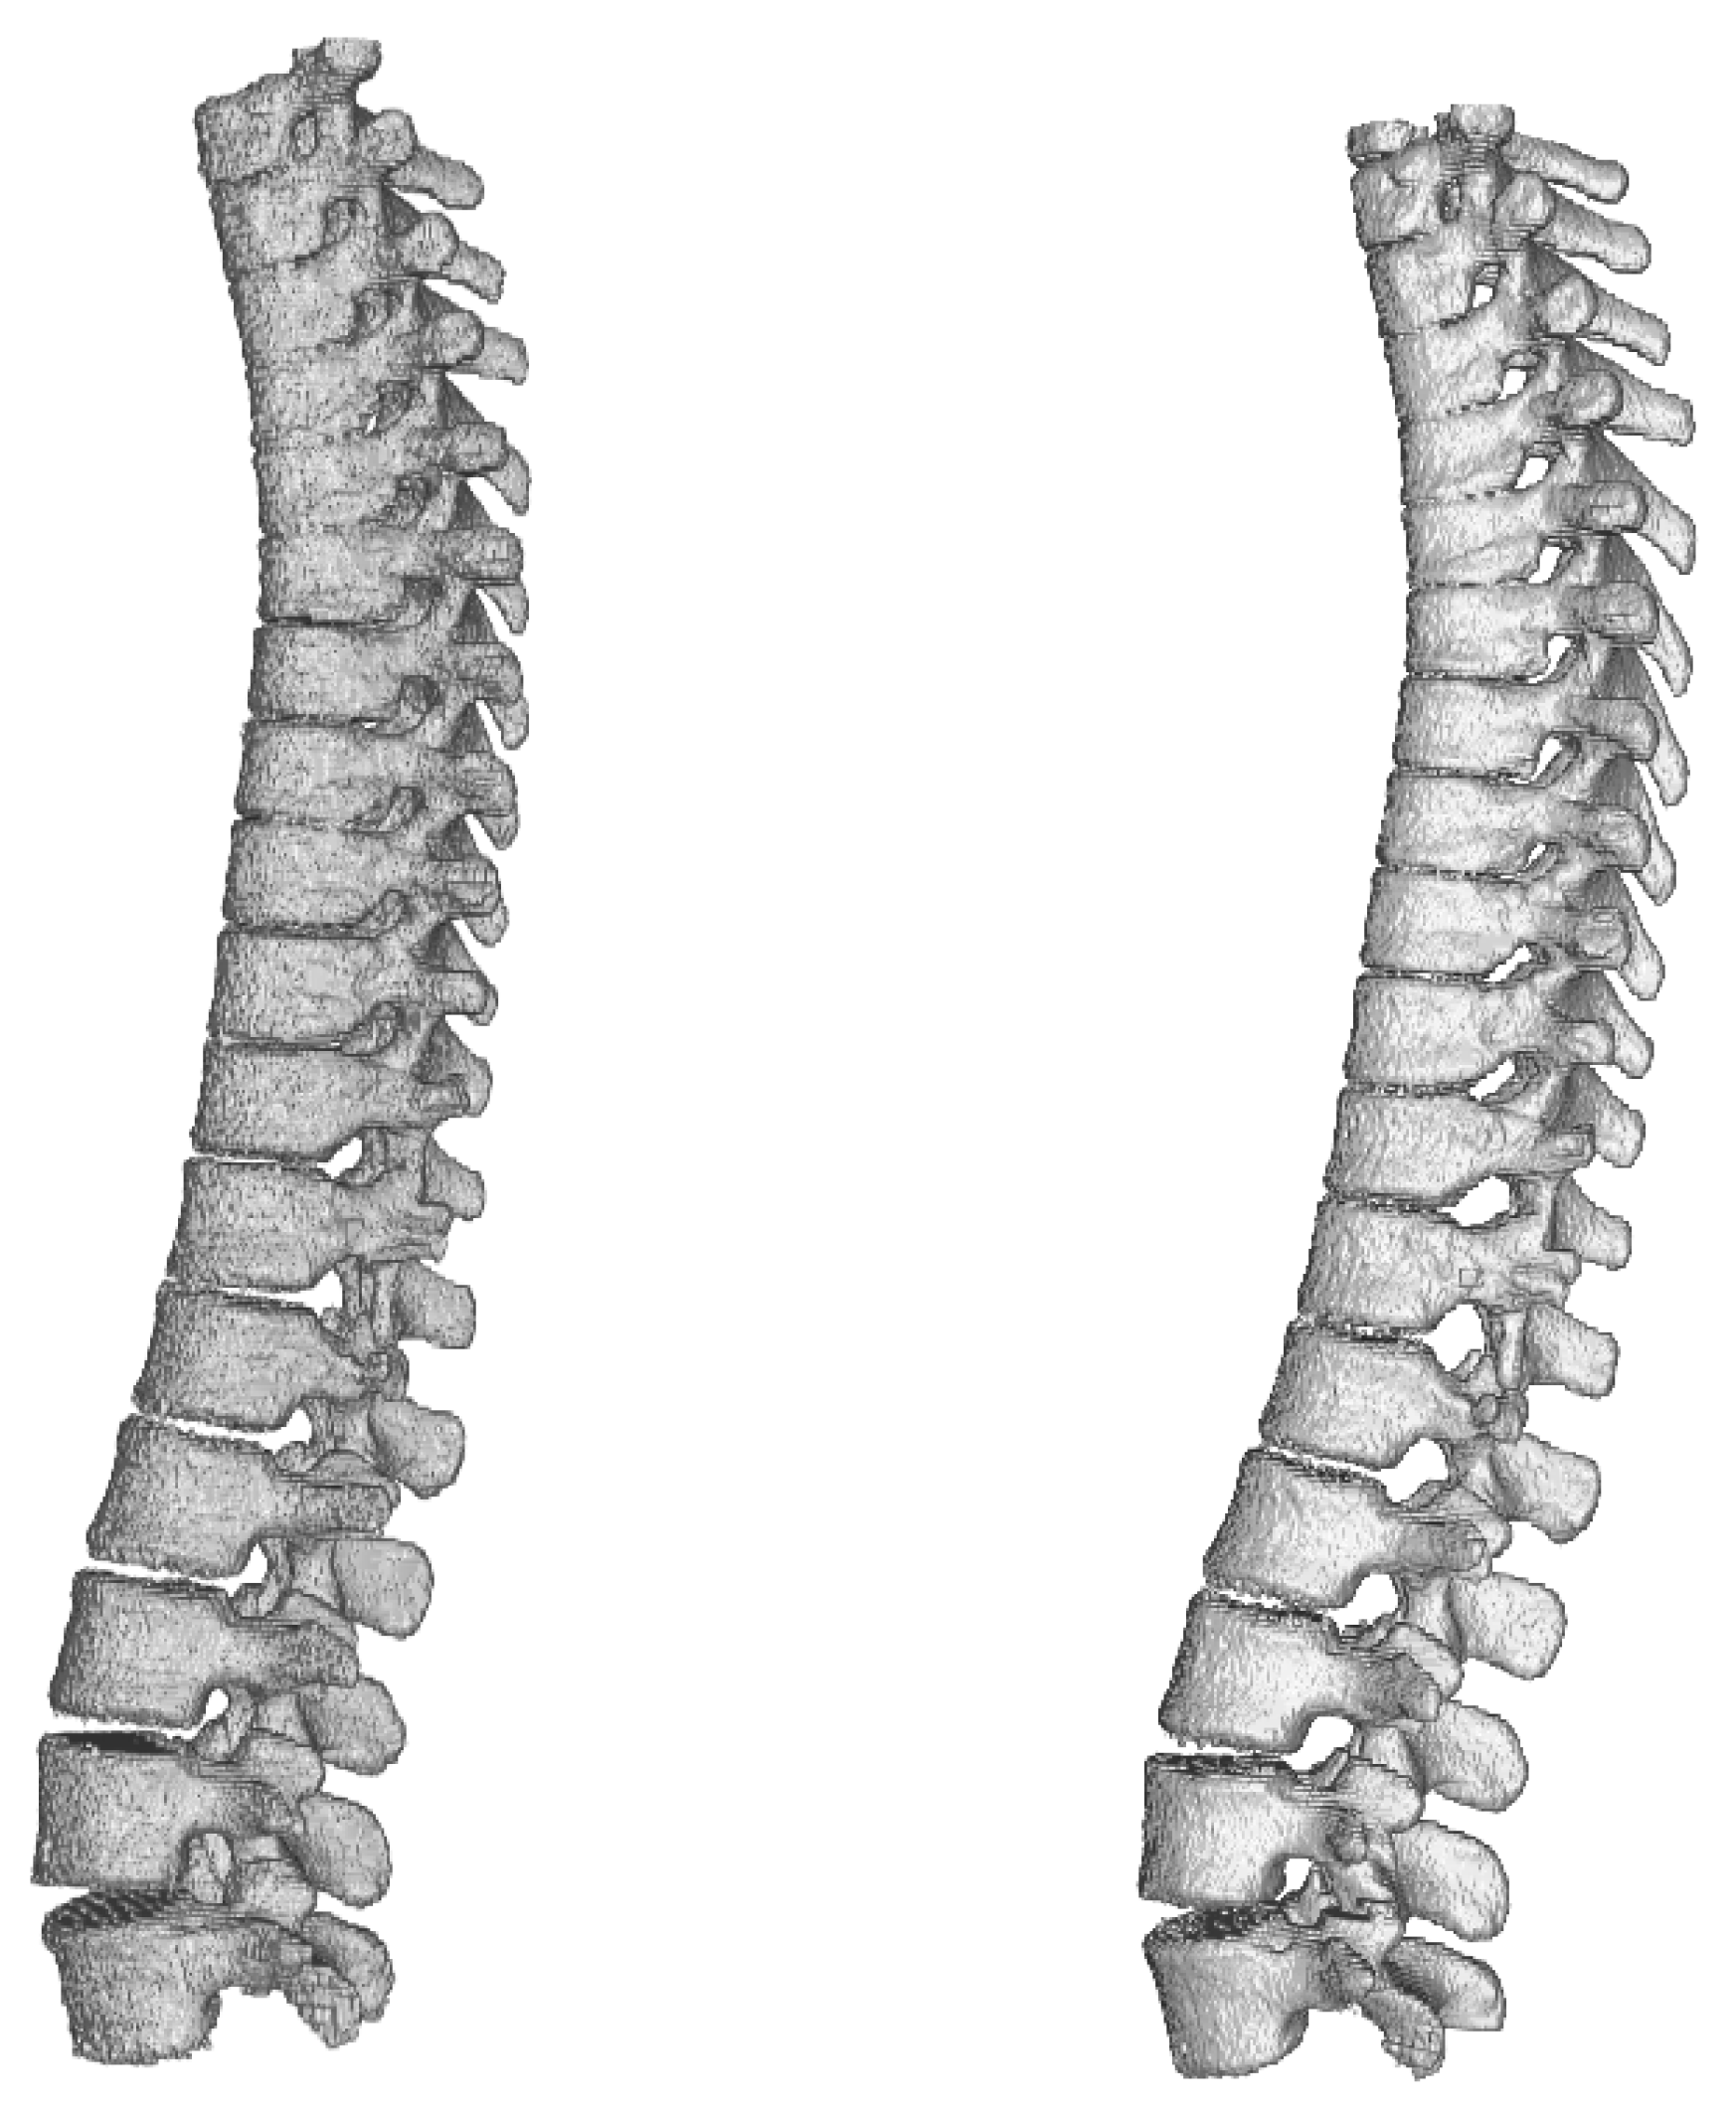

As the benchmark comparison of tested architectures in 2D vs. 3D versions is done on brain dataset, we trained and evaluated only 3D versions of the networks. A comparison of results achieved during benchmark phase using all three architectures can be seen in Table 6 and visualisation of the segmented spine models can be seen in Figure 9. This dataset does not contain second set of labels done by a human expert and therefore the results cannot be compared with human precision.

Figure 9.

Visualisation of segmented spine models from the benchmark training phase. From left to right—Dense-U-Net, Residual-U-Net, U-Net. Please notice that the abnormal vertebrae adhesions exist also in original ground truth masks as can be seen in Figure 10.

Dense-U-Net network has achieved the highest results in all metrics except for average Hausdorff distance. Reason for this is that the model does not perform well on borders of the image. In the dataset there were labelled only thoracic and lumbar vertebrae, but the CT scans contained also the first cervical vertebra and the network did include it in its segmentation results. You can see a part of the first cervical vertebra on top of the segmented spine in Figure 10.

Figure 10.

Comparison of ground truth model (left) and model segmented by Dense-U-Net network (right) after the fine-tuning phase of training. Notice difference on top of the figure—the first cervical vertebra and abnormal vertebrae adhesions that exist also in the original ground truth mask.

After accuracy of Dense-U-Net was verified to outperform the other architectures in the benchmark phase, we trained the network in the fine-tuning phase to achieve the best results possible, now using 99 epochs with weights initialized using pre-trained model. 3-folds cross-validation was used for evaluation. Results of the Dense-U-Net network in fine-tuning phase is depicted in Table 7. The visualisation of fine-tuned Dense-U-Net network result can be seen in Figure 10. Please notice that the abnormal vertebrae adhesions exist also in ground truth masks on the model in Figure 10 and therefore it is not a failure of the segmentation algorithm.